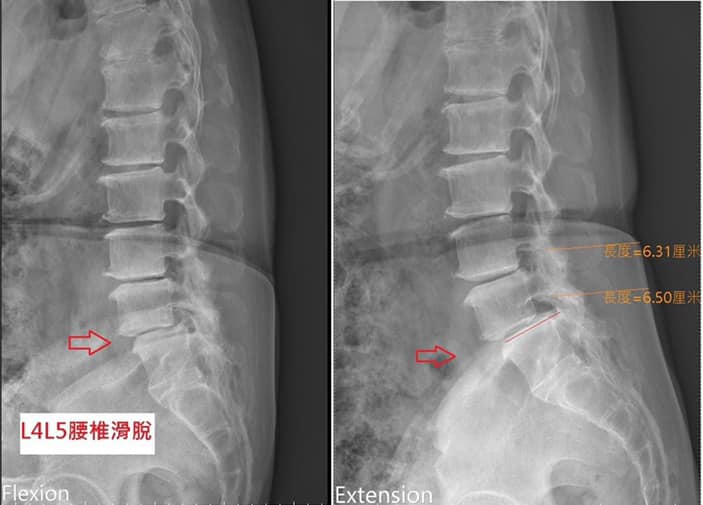

Cervical Spine Treatment Cases 腰椎治療案例 #腰椎手術失敗綜合症候群 #術後沒保養還是又繼續椎間盤突出 #感謝台北梁小姐熱情見證 ... 2021.03.02 #超感動醫案感謝中壢姚阿姨見證 #原本已經坐輪椅的人生看到一絲希望 #脊刻救援牛轉乾... 2021.02.22 #感謝新北中和區陳大哥熱情見證 #從北到南看過眾多中西醫民俗療法 #腰痛到連躺跟坐都... 2021.02.17 #感謝桃園龜山蘆先生熱情見證 #腰椎跟屁股痠痛超過十二年 #腰椎纖維環裂隙導致神經根... 2021.02.16 #騎馬摔傷腰椎醫案 #感謝內湖陳先生熱情見證 #椎間盤突出合併輕微椎間孔狹窄 #重新騎... 2021.02.03 #巨大椎間盤突出醫案 #脊椎整合中醫微創逆轉勝 #感謝三峽林先生熱情見證 #為何突出的... 2021.01.29 #腰椎粉碎性骨折手術後調養醫案 #坐輪椅的人生終於看到希望 #脊椎手術失敗症候群 #Fai... 2021.01.26 #感謝台中市大肚區患者熱情見證 #第二次治療腰痛好超多 #腰酸痛時間快一年了 #親筆寫... 2020.12.05 #腰椎嚴重滑脫醫案 #原本左腳麻痛無法久站超過十分鐘 #脊椎整合中醫微創療法逆轉勝 #... 2020.12.02 #感謝林口楊先生熱情見證 #椎間盤整和中西醫微創療法逆轉勝 #曾經大痛到無法走路嚴重... 2020.11.25 #今天來聊巨大骨刺為何可以吸收回去! #椎間盤突出需要多久才能吸收呢? #馬尾神經症候... 2020.11.10 #腰椎滑脫一定要開刀嗎? #骨科認為開刀置放骨釘穩定錐體 #如果患者可以藉由增強肌... 2020.11.04 #六年的長期腰酸痛醫案 #原來是椎管狹窄合併輕微突出 #每年冬天準時發作苦不堪言 #感... 2020.10.31 #椎管狹窄案例 #感謝新莊陳大哥熱情見證 #腰酸痛數年原來是椎管狹窄 #來診前已經痛到... 2020.10.28 #知名四代魚丸店掌門人熱情見證 #腰椎中醫微創逆轉勝 #椎間盤突出醫案 #感謝新北... 2020.10.23 ← 上一頁 8 9 10 11 12 下一頁 →